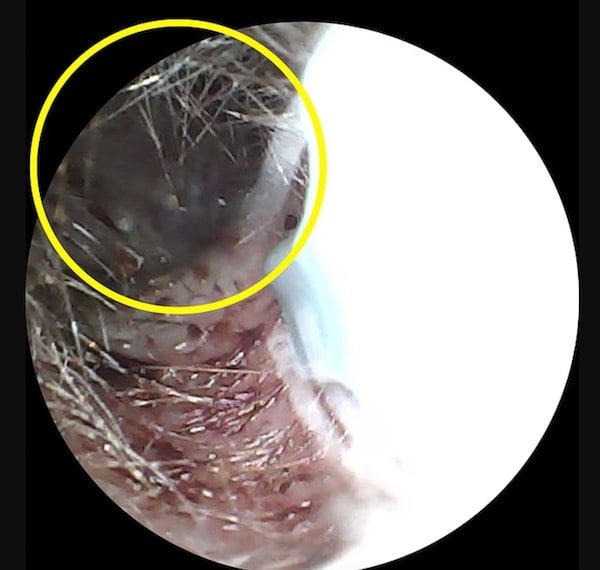

Le moins que l’on puisse dire, c’est que la réalité était tout autre. Et pour cause : l’homme avait un scarabée noir de cinq centimètres coincé dans son oreille. Le coléoptère avait élu domicile au niveau de son tympan.

« C’était horrible. Chaque son qu’il émettait était amplifié à cause de sa proximité du tympan. Et ses pinces me mordaient à l’intérieur de l’oreille, encore et encore…», se souvient le malheureux.

Les docteurs ont utilisé une pommade pour neutraliser l’insecte. Une fois cette étape terminée, ils ont pu l’extraire à l’aide d’un coton, au grand soulagement du patient.